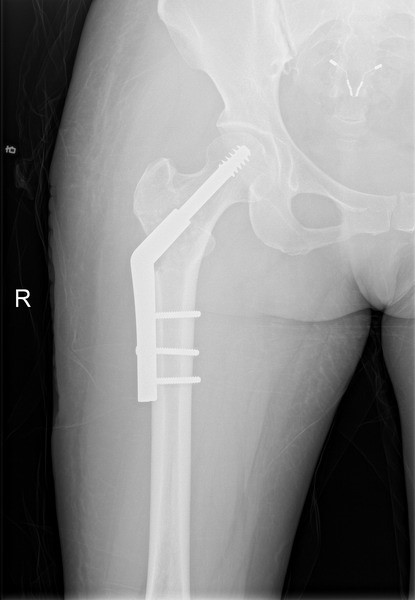

X线改变(2019年):右侧股骨近端局部骨密度不均匀,见大小不等囊性低密度区。

CT(2019年)示:“右侧股骨上段骨质异常密度影,皮质局限性变薄,溶骨性骨破坏。结合病史考虑骨纤维结构不良术后改变,建议必要时MRI检查”。

右侧髋关节MRI(2019年)显示,右侧股骨上段及股骨头不规则增粗,内见团块状异常信号影,T1W1以低信号为主,T2W1呈不均匀高信号,增强不均匀,明显强化,局部骨皮质不连续,内缘欠光整,结合病史考虑纤维结构不良术后改变,不除外恶变可能。 |